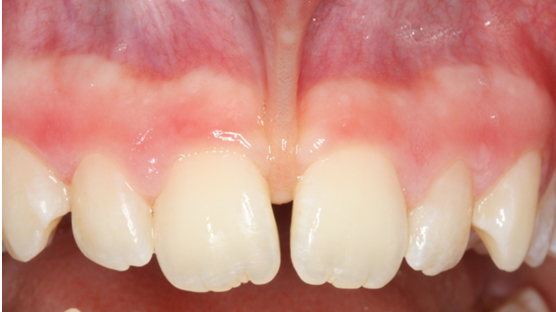

9. Κάλυψη απογυμνωμένων ριζών στην περιοχή κάτω δεξιά (#44-41)

Η ασθενής παρουσίαζε απογύμνωση των ριζών του 1ου προγομφίου και κυνόδοντα κάτω δεξιά και περιορισμένη υποχώρηση ριζών στους κάτω τομείς δεξιά. Πραγματοποιήθηκε πλαστική χειρουργική του περιοδοντίου με τη λήψη μοσχευμάτων ούλων από την περιοχή της υπερώας, η οποία οδήγησε σε πλήρη κάλυψη των ριζών όλων των δοντιών και στους τομείς επιτεύχθηκε και αύξηση του πάχους των ιστών τοπικά.

ΑΡΧΙΚΗ ΚΛΙΝΙΚΗ ΕΙΚΟΝΑ

ΕΙΚΟΝΑ ΕΠΟΥΛΩΣΗΣ 2 ΜΗΝΕΣ ΜΕΤΑ